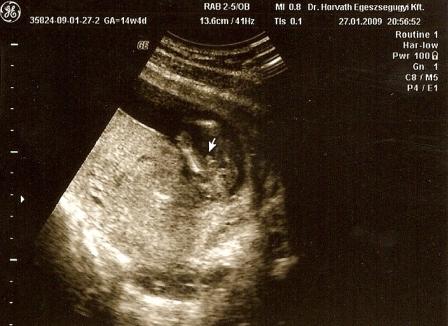

Tegnap reggel én is voltam afp-n. Még jó, hogy úgy voltam vele, hogy nem mondtak semmit, így éhezve megyek, mert nem csak szimpla afp-t vettek, hanem normál vérvételes adatokat is kért a doki.

És hétvégén sikerült beszerezni a szívhanghallgatót is. Kissé ránkjött a frász, amikor apa, Szonji és Marci szíve után sem az enyémet, sem a babaóét nem találtuk meg. Aztán másnap reggel újra próbálkoztunk és akkor már mindkettőnknek dobogott. A fiam úgy hallgatta, olyan édes pofával, hogy szakadtunk a röhögéstől.